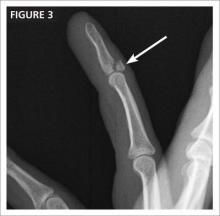

Examination reveals that the injured finger has good capillary refill, 2-point discrimination is intact at 5 mm, and the other fingers on his right hand have no deformities and a normal range of motion. On the injured finger, however, the DIP joint is swollen and tender; it cannot be fully extended (FiGURE 3).

Mallet injuries, which are common in sports and associated with minor trauma, are typically caused by sudden forced flexion of the DIP joint during active extension of the finger. This can either stretch or tear the extensor tendon or lead to avulsion of the tendon insertion from the dorsum of the distal phalanx, with or without a fragment of bone. The injury is called a “soft” mallet finger when there is no bone involvement and a “bony” mallet finger when an avulsion is present, like the one that is evident on the FIGURE 3 x-ray (see arrow).

Surgery is indicated for a fracture fragment involving >30% of the joint surface (as demonstrated in the radiograph), volar subluxation, or a swan neck deformity—and when conservative therapy fails.7